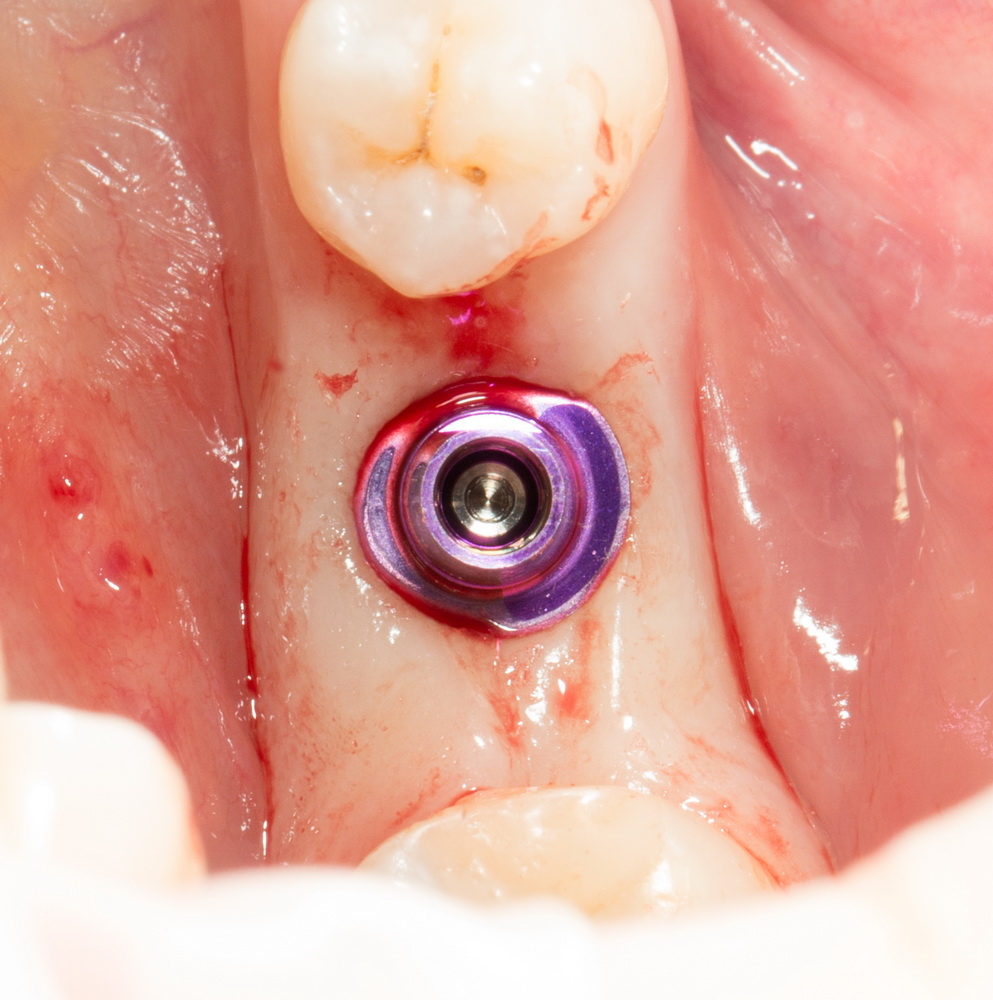

Я же в своей практике для создания доступа использую ультразвук, а именно — электрический пьезохирургический аппарат VarioSurg (NSK). Он позволяет делать очень красивый и практичный доступ любой формы:

- можно сделать доступ любой формы.

Например, в виде сердечка.

- после создания доступа получается костный фрагмент, который мы можем использовать по-разному (для закрытия перфорации, костной пластики,

сварить холодец или чего-нибудь еще)

- можно создавать большие доступы и закрывать их получившимся костный фрагментом, легко обходить септы, шипы и перегородки дна верхнечелюстной полости

- сам процесс создания доступа получается более контролируемым.